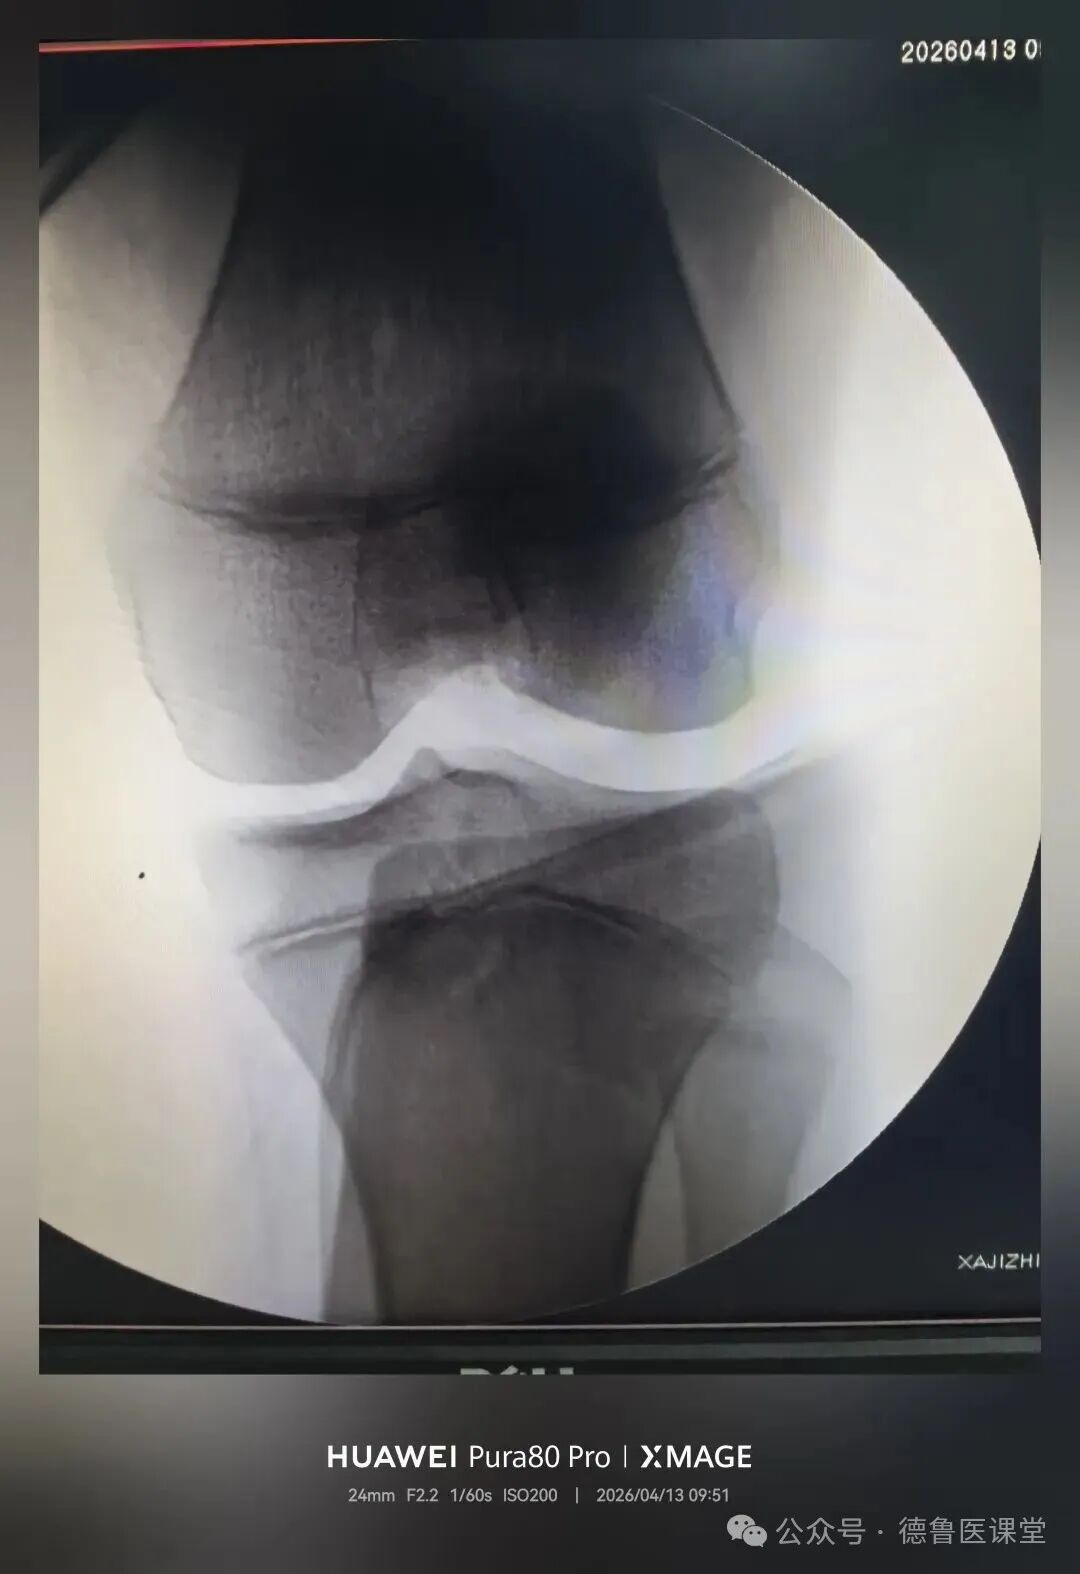

在腘横纹切

疤痕最不明显

对膝关节功能影响最小

术后直接可调式支具固定

逐步指导康复锻炼